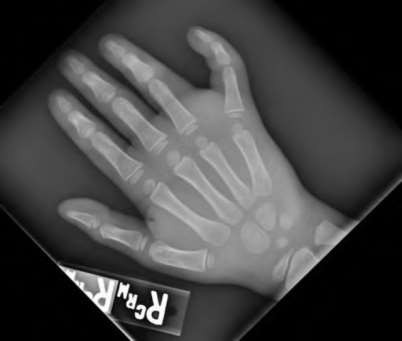

A 35-year-old woman reports wrist pain after a fall onto an outstretched hand. On exam, she has focal tenderness over the wrist snuffbox. A radiograph and CT image are shown in Figures A and B. What is the proper treatment of her injury?